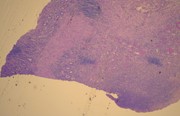

Stage IV sporadic Burkitt's leukaemia with osteolysis in the maxillary sinuses

Yohsuke Yoshioka and others

Journal of Surgical Case Reports, Volume 2016, Issue 2, February 2016, rjw011, https://doi.org/10.1093/jscr/rjw011